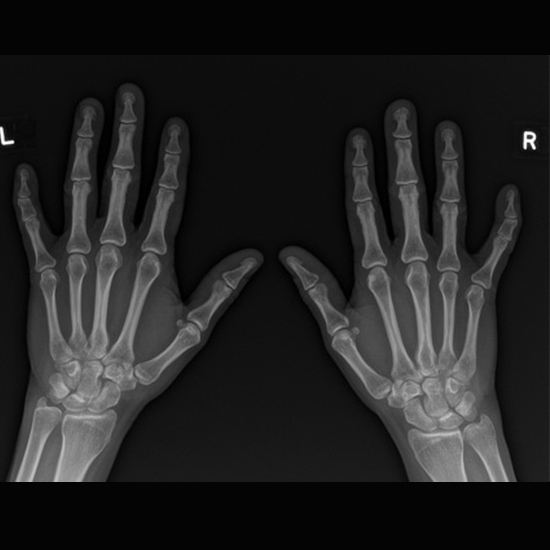

X-Ray Both Hand PA View

X-Ray Both Hand PA (posteroanterior) View is used to view the metacarpals, phalanges, carpal bones, and distal radial ulnar joint. The procedure obtains the x-ray film of the bones and surrounding tissues. Doctors recommend this procedure to assess the hand and detect underlying issues.

Why is X-Ray Both Hand PA View Done?

• The X-Ray Both Hand PA View is ordered to diagnose and detect conditions such as

• Rheumatoid arthritis in the metacarpals, carpal bones, and distal radioulnar joint.

• Osteoarthritis

• Suspected fracture

• Dislocation and localizing foreign bodies.